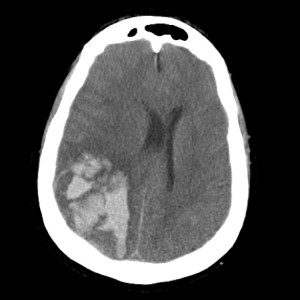

The study is a pooled analysis from the Oxford Vascular Study (OXVASC) and the Lothian Audit of the Treatment of Cerebral Haemorrhage (LATCH). It analyzed 674 first-time ICH patients over 1553 person-years. The cohort’s mean age was 74.7, 47% were male, and 51% were on antithrombotics before their ICH. Additionally, 22% had atrial fibrillation, and 47% had lobar ICH while the rest had non-lobar ICH.

The recurrent ICH rate was 3.2 per 100 person-years based on 46 events in the cohort. The ischemic stroke rate was 1.7 per 100 person-years from 25 events, and the rate for any serious vascular event was 7.9 per 100 person-years from 118 events. Lobar ICH had a higher risk of recurrent hemorrhage with a hazard ratio (HR) of 3.2 (95% CI 1.6-6.3; p=0.0010). Ischemic stroke risk was not location-dependent with an HR of 1.1 (95% CI 0.5-2.8; p=0.76). Atrial fibrillation at the time of the initial ICH increased ischemic stroke risk significantly (HR 8.2, 95% CI 3.3-20.3; p<0.0001).

The study accentuates the importance of two critical risk-stratification parameters for post-ICH management: the anatomical location of the hemorrhage and the presence of comorbid atrial fibrillation. The anatomical location, specifically whether it’s lobar or non-lobar, can be a predictive factor for the likelihood of recurrent hemorrhages. Conversely, atrial fibrillation is a crucial determinant for assessing the heightened risk of ischemic stroke. These risk stratification elements not only lend support to the findings of the RESTART trial but also underscore the urgency for specialized clinical trials that aim at targeted interventions for high-risk subgroups.

In light of recent research, risk stratification in post-ICH management becomes even more critical. A Danish study with 2,819 patients reinforced the Lancet’s findings, showing higher recurrent lobar ICH rates of 3.74 per 100 person-years with an adjusted HR of 2.63 (95% CI 1.97-3.49). The same study emphasized a higher absolute rate of major cardiovascular events (the aggregate of intracerebral hemorrhage, ischemic stroke, non-traumatic extracranial bleeding, myocardial infarction, systemic thromboembolisms, or death due to vascular causes) and myocardial infarctions in non-lobar ICH for those with atrial fibrillation. Another review reported ischemic stroke rates of 3-7% and myocardial infarctions around 4% post-ICH. These recent insights collectively underscore the dire need for targeted clinical trials, particularly involving antithrombotics and statins, to improve secondary prevention strategies in ICH care.

Check out some relevant images from our website below: